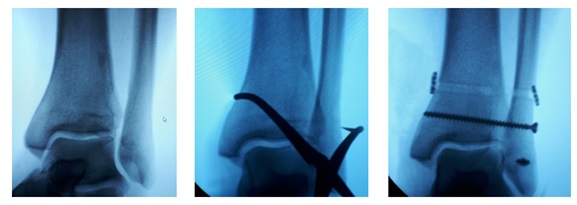

Структура и анатомия синдесмоза: научные иллюстрации